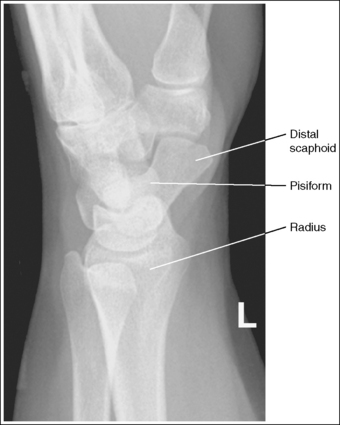

See Figure 4-34 and Box 4-12.

Contrast and density are adequate to demonstrate the scaphoid fat stripe.

• The scaphoid fat stripe is one of the soft tissue structures that should be visible on all PA oblique wrist projections. It is convex and located just lateral to the scaphoid on an uninjured wrist (see Figure 4-30). A change in the shape of this fat stripe or in its proximity to the scaphoid may indicate joint effusion or a radial side fracture.

The wrist has been externally rotated to a 45-degree PA oblique projection. The trapezoid and trapezium are demonstrated without superimposition, and the trapeziotrapezoidal joint space is open. The scaphoid tuberosity and waist are demonstrated in profile. Only a small degree of trapezoid and capitate superimposition is present.

• To accomplish a PA oblique wrist projection, begin with the wrist in a PA projection, with the humerus and the forearm on the same horizontal plane. Externally rotate the hand and wrist until the wrist forms a 45-degree angle with the IR (Figure 4-35). When judging the degree of wrist obliquity, it is best to view the wrist and not the hand. The obliquity of the hand and wrist are not always equal when they are rotated, especially if the humerus and forearm are not positioned on the same horizontal plane for the image.

• Determining the accuracy of wrist obliquity. On a PA wrist projection (see Image 39), the trapezoid and trapezium are superimposed. Placing the wrist in a 45-degree externally rotated PA oblique projection draws the trapezium from beneath the trapezoid, providing clear visualization of both carpal bones and the joint space (trapeziotrapezoidal) between them. The PA oblique projection also rotates the scaphoid tuberosity and waist into profile. The relationships between the trapezoid and trapezium and the trapezoid and capitate are used to discern an accurate PA oblique wrist projection. If the wrist is underrotated, the trapezoid and trapezium are superimposed, the trapeziotrapezoidal joint space is obscured, and the trapezoid demonstrates minimal capitate superimposition (see Image 40). If wrist obliquity is more than 45 degrees, the trapezium demonstrates minimal trapezoidal superimposition, the capitate is superimposed by the trapezoid, and the trapeziotrapezoidal joint space is obscured (see Image 41).

The second CM and the scaphotrapezoidal joint spaces are demonstrated.

The long axes of the third metacarpal and midforearm are aligned with the long axis of the collimated field. The scaphoid tuberosity and waist are demonstrated in profile and are not positioned directly next to the radius.

• If the long axes of the third metacarpal and midforearm are aligned with the long axis of the collimation field, the patient's wrist is placed in a neutral position. Radial deviation increases the foreshortening of the scaphoid, preventing visualization of the scaphoid tuberosity and waist, and positions the scaphoid directly next to the radius (see Image 42). Ulnar deviation decreases scaphoid foreshortening (see Image 43).

The ulnar styloid is in profile at the far medial edge.

• The position of the humerus and elbow determines the placement of the ulnar styloid. The ulnar styloid is demonstrated in profile when the patient's humerus is abducted to align the humeral epicondyles perpendicular to the IR and place the elbow in a lateral position. If the humerus is not abducted to this degree, the ulnar styloid is no longer demonstrated in profile.

The carpal bones are at the center of the exposure field. The carpal bones, one fourth of the distal ulna and radius, and half of the proximal metacarpals are included within the collimated field.

• The wrist joint is located at the base of the first proximal metacarpal. To obtain a PA oblique projection of the carpal bones with the least amount of distortion, place a perpendicular central ray at this level and centered with the midwrist area. Open longitudinal collimation to include half of the metacarpals. Transversely collimate to within 0.5 inch (1.25 cm) of the wrist skin line.